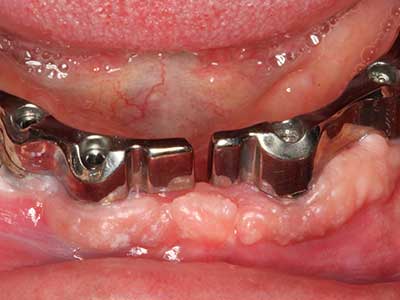

Bei der Knochenblockentnahme zeigen sich weitere Vorteile für die Piezochirurgie: Neben der bereits beschriebenen hohen Präzision bei der Osteotomie stellt sich gerade die Verwendung der dünnen Sägespitzen als besonders materialschonend heraus. Bei der Verwendung insbesondere von Lindemannfräsen sind mit deutlich höheren Entnahmeverlusten durch die dickere Instrumentenspitze zu rechnen (Lakshmiganthan, Gokulanathan et al. 2012). Die insbesondere bei retromolar entnommenen Blocktransplantaten notwendige basale Abtrennung wird durch speziell hierfür vorgesehene rechtwinklige Sägen erleichtert, so dass die Piezochirurgie als präzises, übersichtliches und sicheres Verfahren zur retromolaren Knochenblockgewinnung angesehen wird (Happe 2007) (Abb. 1-12).

Marginale Parondontalerkrankungen stellen im fortgeschrittenen Alter den Hauptgrund für Extraktionen dar. Sie basieren im Wesentlichen auf einer bakteriellen Besiedlung der Zahnfleischtasche und hierdurch bedingten Entzündung mit konsekutivem Verlust des Zahnhalteapparates. Die Ausbildung subgingivaler Biofilme und Konkremente stellt einen wesentlichen ätiologischen Faktor für den marginalen Knochenabbau dar, so dass ihrer Entfernung eine wesentliche Bedeutung in der Therapie zukommt (Drisko 2014, Plessas 2014).

Zur Behandlung einer marginalen Parodontitis lassen sich eine initiale und chirurgische Therapiephase unterscheiden. Neben der Mundhygieneinstruktion und -motivation sollte in beiden Phasen eine suffiziente Reinigung der Wurzeloberfläche erfolgen, wobei im regenerativen Setting zumeist ein offener Zugang gewählt wird. Die Reinigung der Wurzeloberfläche kann durch die Verwendung spezieller Ansätze auch piezochirurgisch erfolgen, wobei unterschiedlich gebogene Instrumente auch schlecht zugängliche Bereiche wie Furkationen erreichen. Die systemimmanente Wasserkühlung spült dabei die gelösten Konkremente und Bakterien aus der Tasche. Um zusätzlich die Abtragung von Zahnhartsubstanz zu minimieren, wurde bei speziellen Systemen wie dem Piezomed ein Applikations-Feedback eingebaut. Hierbei wird die Abtragungsleistung konsequent reduziert, je mehr Druck auf den Parodontalansatz ausgeübt wird.